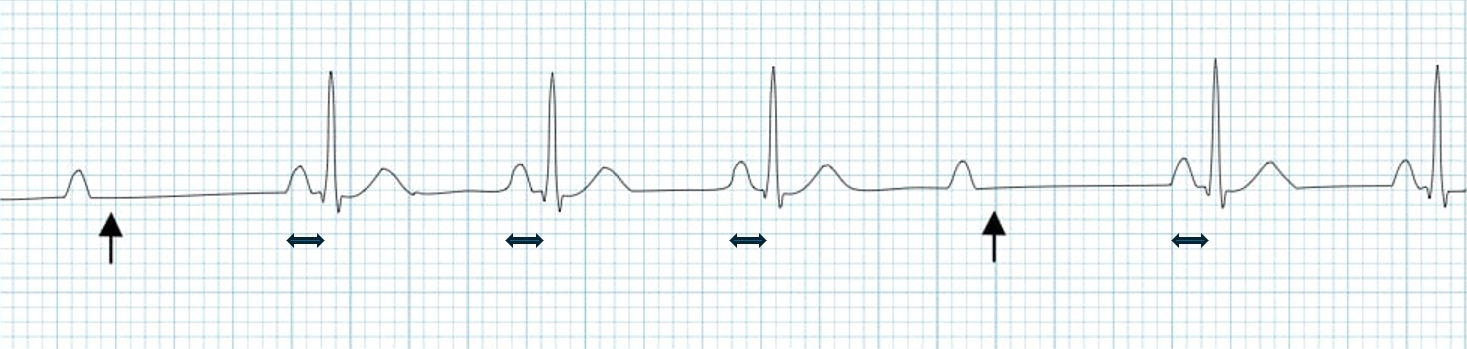

Chest Leads Placement

| Electrode | Placement Location |

|---|---|

| V1 | 4th intercostal space, right sternal border |

| V2 | 4th intercostal space, left sternal border |

| V3 | Midway between V2 and V4 |

| V4 | 5th intercostal space, mid-clavicular line |

| V5 | Same level as V4, anterior axillary line |

| V6 | Same level as V4, mid-axillary line |

Since V3 is placed midway between V2 and V4, the practical order of placing ECG leads is V1 and V2 → V4 → V3 → V5 and V6.

The correct placement of chest lead electrodes is commonly featured in both written exams and OSCEs.